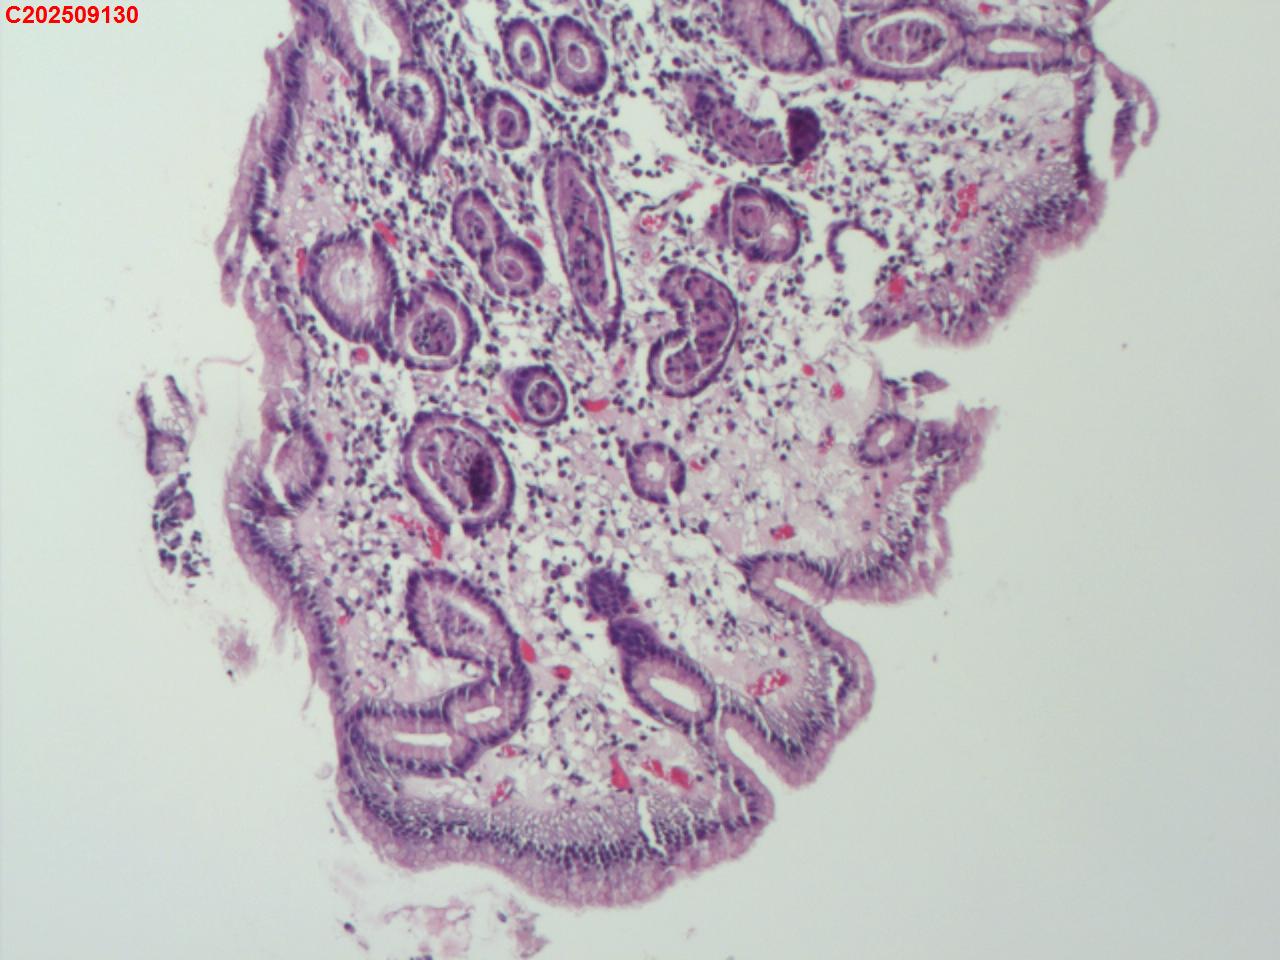

胃体粘膜

性别

女

年龄

76岁

临床诊断

胃息肉

一般病史

体检

标本名称

大体所见

胃体大弯可见一枚直径约2mm息肉样隆起

增生性息肉。